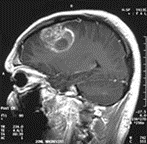

La curiethérapie ou brachythérapie est une technique de traitement du cancer consistant à déposer une source radioactive au contact ou au sein de la tumeur de manière à cibler directement la zone atteinte par le cancer. À titre d’exemple, aucun traitement n’a encore été trouvé pour le glioblastome, une tumeur maligne primaire du cerveau. Des nanoparticules vecteurs d’atomes radioactifs (rhénium-188) sont proposées pour éliminer les cellules tumorales laissées en place après chirurgie d’exérèse. Dans le travail que nous avons conduit, des microparticules à base d’oxyde d’Holmium enrobées de polysiloxane d’une taille de l’ordre du micromètre ont été sélectionnées pour cette application. Ces suspensions sont considérées comme des dispositifs médicaux. Le choix des indications ciblées en priorité au cours de ce projet est basé sur des considérations précliniques, règlementaires et d’accès au marché. Les techniques de A4F permettront de s’assurer de l’intégrité (ou non) de l’ensemble de ces nanoparticules. En vue de proposer des outils et des indicateurs pour le développement de ces objets en phase clinique, tout un arsenal de caractérisations physico-chimique a été développé (zéta, microscopies, DLS, ATG …). Ce travail a été réalisé en collaboration avec des industriels (Advanced Accelerator Applications, Nano-H, Gi-Pharma), et les Universités de Limoges et Lyon I.